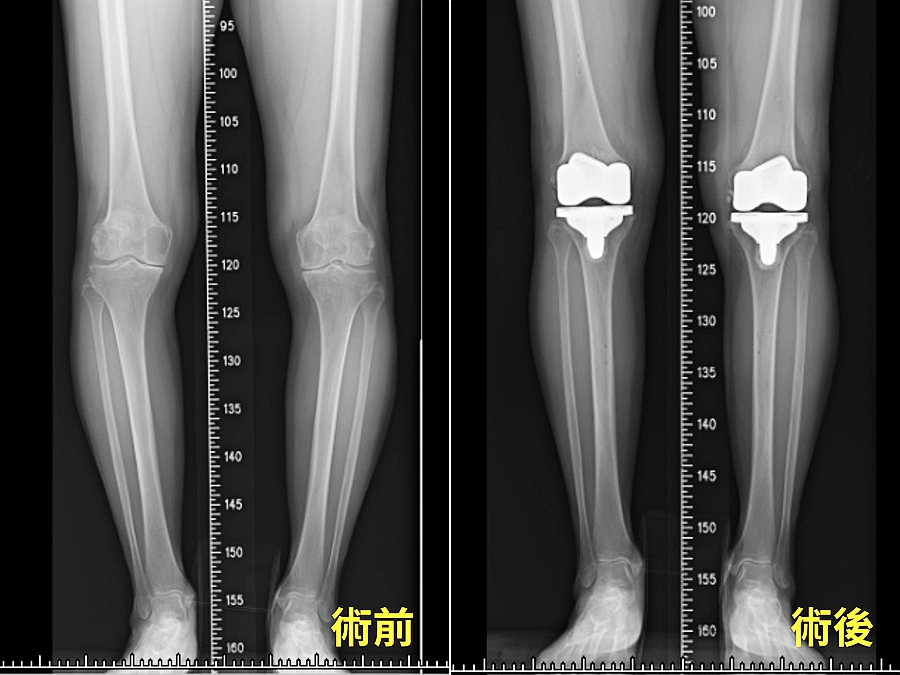

陳女士說,她的膝關節庝痛已持續7、8年,之前還能勉強忍受,但在去年底的一次健行爬山中痛到完全無法行走,透過朋友介紹,前往長安醫院骨科尋求幫助。楊醫師檢查後發現,她的退化性關節炎已屬於第四期,並且已經出現O型腿的變形,經過討論後,決定接受恢復比較快的微創機器手臂關節置換術。

楊志鴻醫師表示,精準定位是膝關節置換手術成功的關鍵,而這正是Mako®機器手臂的優勢所在。它能根據患者的膝關節角度及下肢軸線,精確設計出最適合的人工關節尺寸及擺放位置。與傳統手術相比,Mako®機器手臂不僅能縮小手術傷口,還能保留健康的骨本和韌帶組織,使患者術後恢復更快。